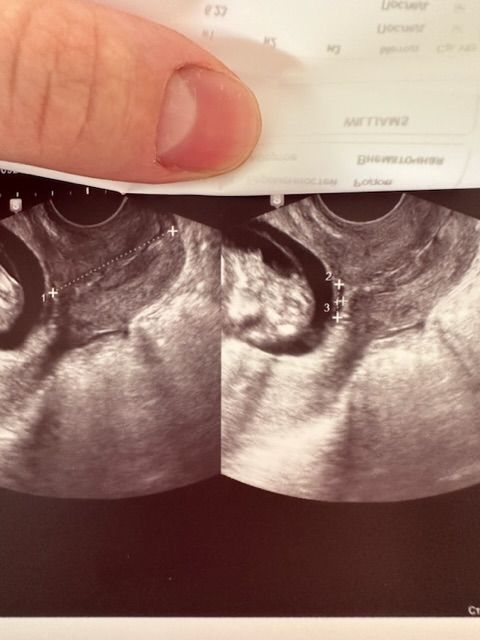

Небольшой участок отслойки плодных оболочек

Девочки помогите понять это не критичные размеры отслойки ? Крови не было живот не болит . Как понимать , размер пишет 8,5*1,8 мм